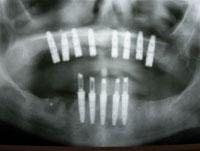

Figure 15 - Panoramic radiograph verifying dental implant placement and immediate load of the mandibular implants with a fixed prosthesis

Upon delivery of the prosthesis to the patient, the occlusion was verified, the screws hand-tightened, and a cotton pellet and Cavit™ were placed in the access hole (Figure 14). Instructions for care and maintenance were provided to the patient with emphasis on a relatively soft diet for six to eight weeks with no parafunctional loading of the implants (Figure 15). After healing, final impressions will be made and a definitive prosthesis fabricated and delivered.